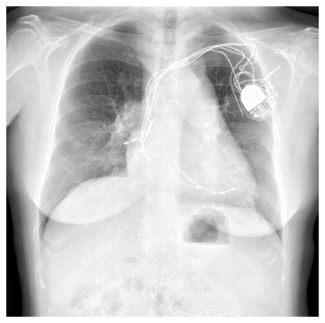

Case Report 1. A 63-year-old female patient with a past medical history significant for bilateral breast cancer status post bilateral mastectomies, chemotherapy, and radiation therapy presented with a 6-week history of slowly increasing swelling in her upper arms and neck. Her symptoms became suddenly worse 6 days prior to her ER visit and were associated with headaches and orthopnea. Prior to her admission, a chest CT scan with contrast was performed at an outside institution and was inconclusive. Given her clinical  presentation and the fact the she still had a venous port in her right subclavian vein, she was brought straight to the catheterization lab. Following informed consent and moderate sedation, an 8 Fr Pinnacle sheath (Terumo) was placed through the right femoral vein. A venogram of the SVC showed 100% occlusion (Figure 1). After infusion of 4000 international units of IV heparin, a 70 cm 8 Fr cook sheath (Cook Medical) was introduced. Using a Berenstein catheter (AngioDynamics) and a Glidewire

presentation and the fact the she still had a venous port in her right subclavian vein, she was brought straight to the catheterization lab. Following informed consent and moderate sedation, an 8 Fr Pinnacle sheath (Terumo) was placed through the right femoral vein. A venogram of the SVC showed 100% occlusion (Figure 1). After infusion of 4000 international units of IV heparin, a 70 cm 8 Fr cook sheath (Cook Medical) was introduced. Using a Berenstein catheter (AngioDynamics) and a Glidewire  (Terumo), the SVC occlusion was crossed and a venogram of the left internal jugular vein (LIJ) revealed a 100% stenosis of the distal LIJ and left subclavian system. An 8 Fr Trellis was then placed (Figure 2), isolating a 15 cm treatment zone between the SVC and the LIJ. We delivered 10 mg of t-PA over 12 minutes with complete removal of the thrombus. Another venogram of the SVC showed a right innominate vein thrombus. Using a Berenstein catheter (AngioDynamics), we then crossed with an exchange-length Wholey wire (Mallinckrodt) to the right internal jugular vein (RIJ). An 8 Fr Trellis with a 15 cm treatment zone was advanced into the right subclavian vein (RSV) and 10 mg of t-PA were delivered between the SVC and the RSV over a 10-minute period. Following thrombus aspiration, scar around the port just distal to the SVC was noted and was dilated with 10 mm x 40 mm and 12 mm x 40 mm Agiltrac balloons (Abbott Vascular), with excellent results (Figure 3). Patient’s symptoms improved substantially during her hospital stay and she remained asymptomatic at her 6 months post-procedural follow-up visit.

(Terumo), the SVC occlusion was crossed and a venogram of the left internal jugular vein (LIJ) revealed a 100% stenosis of the distal LIJ and left subclavian system. An 8 Fr Trellis was then placed (Figure 2), isolating a 15 cm treatment zone between the SVC and the LIJ. We delivered 10 mg of t-PA over 12 minutes with complete removal of the thrombus. Another venogram of the SVC showed a right innominate vein thrombus. Using a Berenstein catheter (AngioDynamics), we then crossed with an exchange-length Wholey wire (Mallinckrodt) to the right internal jugular vein (RIJ). An 8 Fr Trellis with a 15 cm treatment zone was advanced into the right subclavian vein (RSV) and 10 mg of t-PA were delivered between the SVC and the RSV over a 10-minute period. Following thrombus aspiration, scar around the port just distal to the SVC was noted and was dilated with 10 mm x 40 mm and 12 mm x 40 mm Agiltrac balloons (Abbott Vascular), with excellent results (Figure 3). Patient’s symptoms improved substantially during her hospital stay and she remained asymptomatic at her 6 months post-procedural follow-up visit.

Case Report 2. A 45-year-old woman with a history of right-sided breast cancer diagnosed 1 year prior to her admission presented to an outside hospital with a 6-week history of slowly progressing neck, facial, breast swelling, and shortness of breath. A CT scan of the chest showed near complete occlusion of the superior vena cava. Patient was transferred to our center for further management. She had received multiple upper extremity ports and catheters over the last year and had a left subclavian line still in place upon presentation.

Case Report 2. A 45-year-old woman with a history of right-sided breast cancer diagnosed 1 year prior to her admission presented to an outside hospital with a 6-week history of slowly progressing neck, facial, breast swelling, and shortness of breath. A CT scan of the chest showed near complete occlusion of the superior vena cava. Patient was transferred to our center for further management. She had received multiple upper extremity ports and catheters over the last year and had a left subclavian line still in place upon presentation.  A venogram was obtained using her left subclavian port. The SVC, RIJ, and right brachiocephalic vein were occluded (Figure 4). The right internal mammary vein was large and provided many venous collaterals. We then accessed the right femoral vein, introduced a 10 cm 8 Fr Pinnacle sheath (Terumo) and crossed the obstruction using a 0.035 Glidewire (Terumo) and a 5 Fr angled-tip Berenstein catheter (AngioDynamics). After confirming we were in the true lumen of the RIJ, we exchanged for a Rosen wire

A venogram was obtained using her left subclavian port. The SVC, RIJ, and right brachiocephalic vein were occluded (Figure 4). The right internal mammary vein was large and provided many venous collaterals. We then accessed the right femoral vein, introduced a 10 cm 8 Fr Pinnacle sheath (Terumo) and crossed the obstruction using a 0.035 Glidewire (Terumo) and a 5 Fr angled-tip Berenstein catheter (AngioDynamics). After confirming we were in the true lumen of the RIJ, we exchanged for a Rosen wire  (Infiniti Medical) and introduced an 8 Fr Trellis device with a 15 cm treatment zone. After isolating the segment between the RIJ and the SVC/right atrial junction (Figure 5), we infused 11 mg of t-PA over 12 minutes. Following restoration of flow, a severe stricture was seen in the SVC and the brachiocephalic vein. We then dilated the brachiocephalic vein using an 8 mm x 60 mm Agiltrac balloon (Abbott) at 6 and 12 atm, and dilated the SVC using a 12 mm x 40 mm Foxcross balloon (Abbott) at 8 atm in graded increases of 4 atm. We checked for a pressure gradient between the RIJ and the right atrium using a 6 Fr multipurpose catheter (Boston Scientific), a 0.018 wire, and a Tuohy system (Boston Scientific). The maximal pressure difference was less than 5 mmHg. A venogram was performed and showed good flow restoration across the brachiocephalic and SVC (Figure 6). Patient felt a decrease in her neck swelling and shortness of breath while on the table within a few minutes following the end of the procedure. She was still asymptomatic and feeling great at 3 months follow-up and was later seen by her primary oncologist for continued work-up for cancer.

(Infiniti Medical) and introduced an 8 Fr Trellis device with a 15 cm treatment zone. After isolating the segment between the RIJ and the SVC/right atrial junction (Figure 5), we infused 11 mg of t-PA over 12 minutes. Following restoration of flow, a severe stricture was seen in the SVC and the brachiocephalic vein. We then dilated the brachiocephalic vein using an 8 mm x 60 mm Agiltrac balloon (Abbott) at 6 and 12 atm, and dilated the SVC using a 12 mm x 40 mm Foxcross balloon (Abbott) at 8 atm in graded increases of 4 atm. We checked for a pressure gradient between the RIJ and the right atrium using a 6 Fr multipurpose catheter (Boston Scientific), a 0.018 wire, and a Tuohy system (Boston Scientific). The maximal pressure difference was less than 5 mmHg. A venogram was performed and showed good flow restoration across the brachiocephalic and SVC (Figure 6). Patient felt a decrease in her neck swelling and shortness of breath while on the table within a few minutes following the end of the procedure. She was still asymptomatic and feeling great at 3 months follow-up and was later seen by her primary oncologist for continued work-up for cancer.